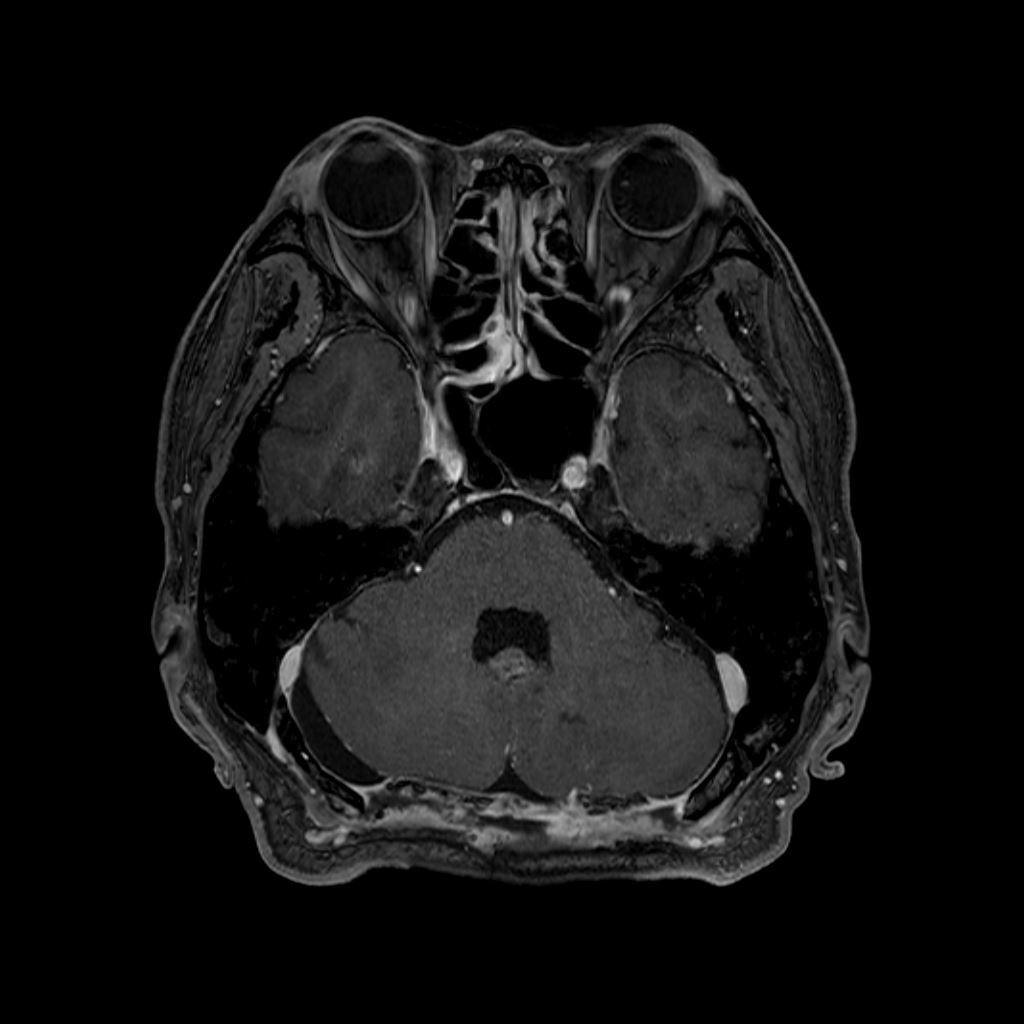

第四脳室髄膜腫術前

術後

脳腫瘍の開頭手術は、全身麻酔下で頭皮を切開し頭蓋骨を開けて、顕微鏡やナビゲーション装置を用いて脳腫瘍をできる限り安全に摘出する手術です。癒着している腫瘍と周囲の神経や血管を慎重に剥離しながら摘出を進めます。術中は電気生理学的検査や神経モニタリングで脳機能をチェックしつつ、安全に最大限の摘出を目指します。ナビゲーションや内視鏡などの技術を用いて低侵襲化や機能温存を検討しています。手術の進め方は腫瘍の種類(良性か悪性)、場所、大きさ、患者の状態により最適化され、機能温存を重視して部分摘出にとどまるケースもあります。